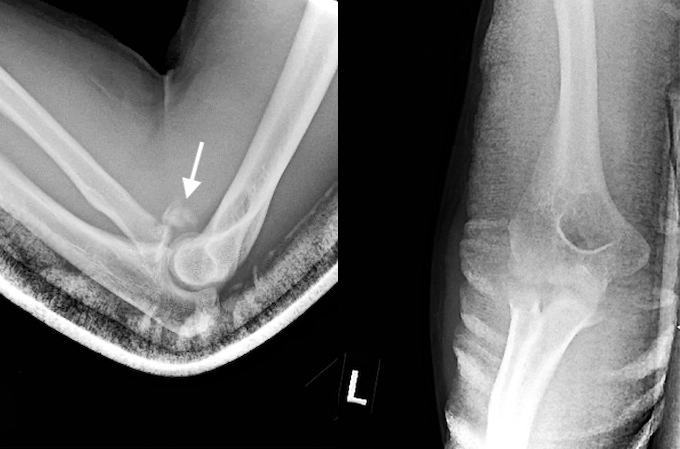

- The terrible triad injury (TTI) of the elbow involves a radial head fracture combined with an elbow dislocation and ulnar coronoid process fracture. This injury has earned its nickname because it is very challenging to treat successfully.13,15

- TTIs are typically caused by a high-energy FOOSH.13

- These injuries are relatively rare, accounting for about 8–11% of all elbow dislocations and 3–10% of all radial head fractures.13

Imaging

- Radiology studies - X-ray

- Magnetic resonance imaging - MRI without contrast

- Radiology studies - Computerized tomography (CT) scanning